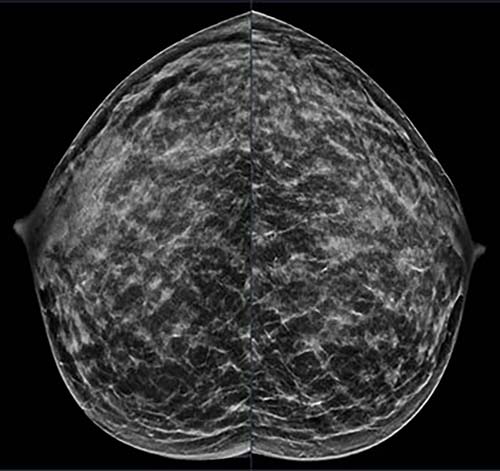

Figure 1. 40-year-old patient presents for routine screening. Family history of paternal grandmother age 55. Extremely dense breast tissue is noted on mammography right and left craniocaudal (taken from the top of the breast) view.

Figure 2. 40-year-old patient presents for routine screening. Family history of paternal grandmother age 55. Extremely dense breast tissue is noted on mammography right and left mediolateral oblique (side angle) view. In addition, an area of architectural distortion is seen at the posterior right breast on right view (see arrow).